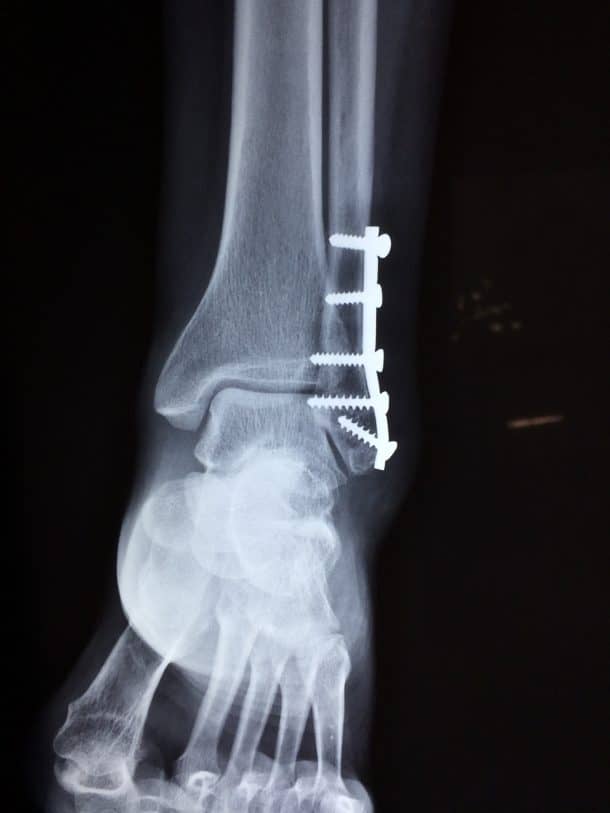

如果你曾经断过胳膊或腿,你就知道愈合的过程有多漫长,有多痛苦。在骨折愈合的过程中,通常会插入螺钉和钉子将骨折的碎片固定在一起。医疗技术的突破可能会使这些做法过时。爱游戏ayx体育

这项新技术包括3爱游戏ayx体育D打印陶瓷植入物,它可以将骨折的骨头固定在一起,同时本身变成真正的骨头。这些植入物是由澳大利亚悉尼大学的Hala Zreiqat和她的同事发明的。